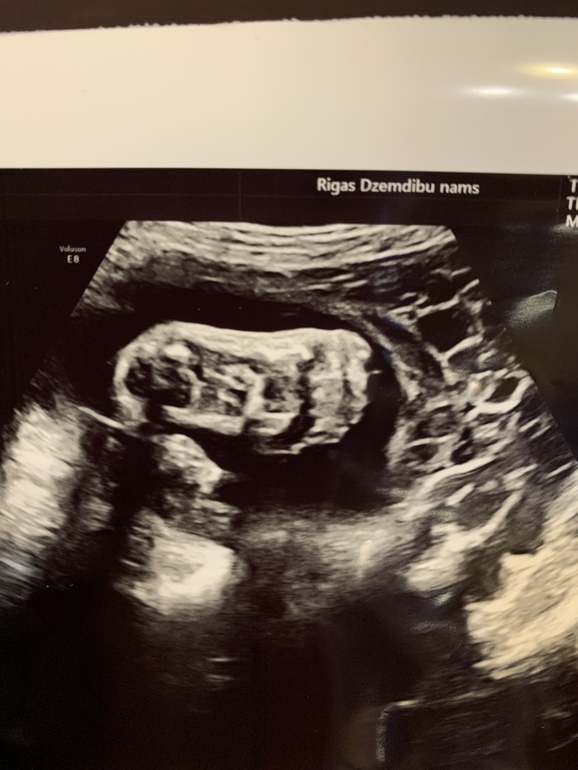

А тем временем идёт 31-я неделя. По плоду 32-я... Я больше не работаю. И понимаю, что лень напала))) Валяюсь дома, гуляю редко. Постоянно за рулем. А надо бы чаще бывать на свежем воздухе. Сегодня была на УЗИ. Плод, по всем параметрам соответствует 33 полным неделям! Опять ждать мне слонёнка))) Ну и фото нас на память. И просто и с узи.

Все фото узи - как на подбор крутые! Первый раз вижу столько удачных за одно узи)молодец малыш😊